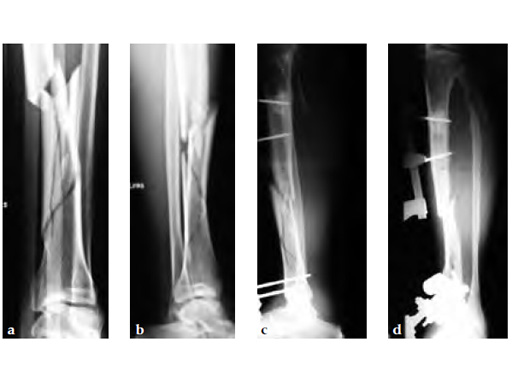

Secondary treatment: insertion of an unreamed intramedullary nail with three ASLS screws inserted distally providing angular stability.

Partial weight bearing started on postoperative day 2 (with 2030kg). The weight was gradually increased over the following weeks. At 6 weeks, the patient was able to fully bear weight even though a high fibula fracture was present and no callus had yet formed. This suggests that angular stable interlocking of the nail markedly enhances stability. The patient was able to bear weight faster than planned and full weight bearing was possible with little pain.

Twelve-week follow-up shows callus formation, and the patient was able to fully bear weight without any pain.

The nail was removed 15 months postinjury as planned. There is good callus formation and proper healing of the tibia fracture.